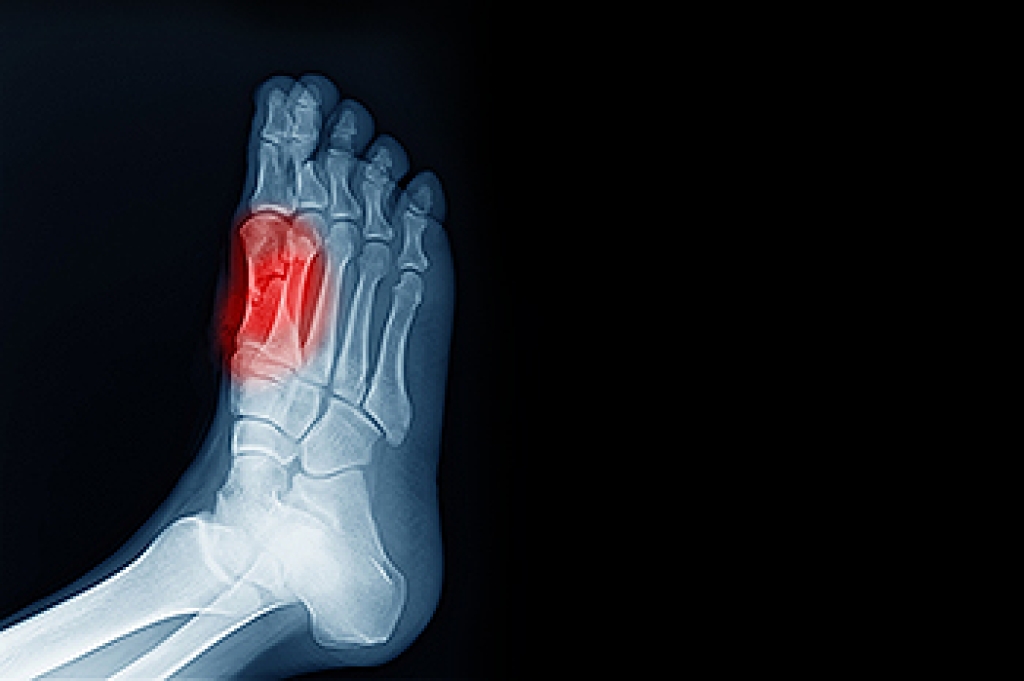

In many cases the cause of toe pain is obvious, but in others, a podiatrist may want to use more advanced methods to determine the problem. These can range from simple visual inspections and sensation tests to X-rays and MRI scans. Prior medical history, family medical history, and any recent physical traumatic events will all be taken into consideration for a proper diagnosis.

• Fractures (broken bones)